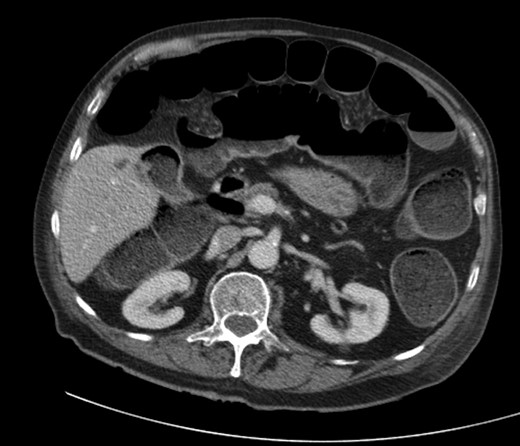

A 92-year male, with no significant co-morbidities apart from peptic ulcers, was admitted with 6 days of obstination. On examination he was dehydrated, with a hugely distended abdomen but no signs of peritonitis. Blood showed features of dehydration and plain abdominal X-ray demonstrated both small and large bowel dilatation, but no obvious causal pathology. A contrast-enhanced computed tomography scan revealed a 2.5-cm partially calcified gallstone impacted at the descending colon-sigmoid junction (Fig. 1). There was no stricture or diverticular disease distal to the stone. A cholecysto-colic fistula could be seen (Fig. 2), with a further smaller gallstone in the caecum (Fig. 3). The offending gallstone could be seen incidentally in the gallbladder on imaging 3 years previously (Fig. 4).

CT reconstruction showing the impacted gallstone and a smaller incidental gallstone in the caecum.